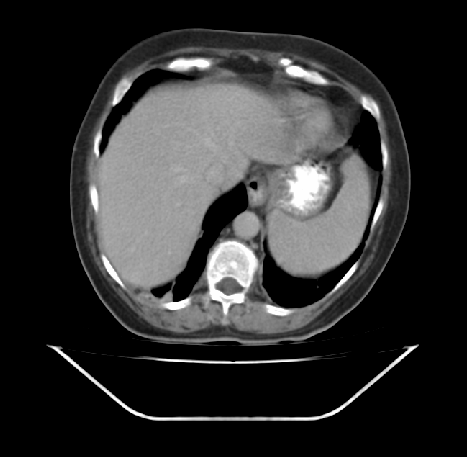

ist jemand unter Euch der sich auskennt mit CT Aufnahmen ?

Ich habe 3 Stück angehangen, sie stammen aus einem CT der Abdomen.

Möglich das es eine Serie eines Querschnitts darstellt Bild 1 zeigt den Start,Bild 2 eines aus den mittleren Aufnahmnen und Bild 3 das letzte dieser CT Serie.

Da ganz gezielt auf ein und die gleiche Stelle gehalten wurde mit sagenhaften über 80 Einzelaufnahmen interessiert mich brennend um die Darstellung welches Organges es sich bei diesen Aufnahmen handelt und ob darauf etwas bedenkliches eingekreist wurde.